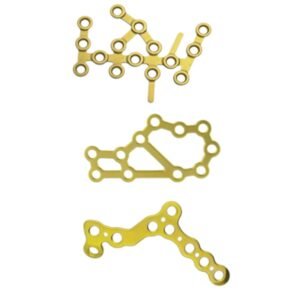

- Placa Bloqueada, Trauma

Placa para manos y pies

- Fracturas, osteotomías y artrodesis de mano y pie.